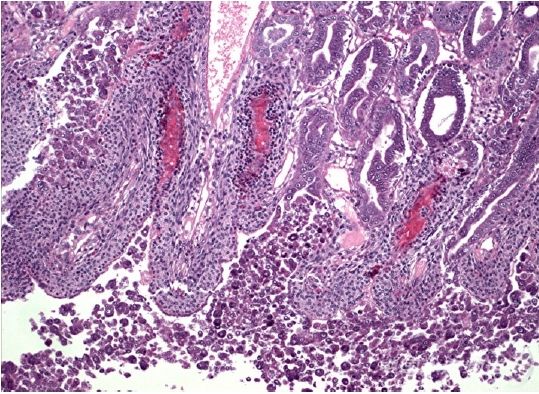

急性肝胰腺壞死綜合癥(AHPNS)的案例分析(參考Don Ligntner 教授的演講) 這次疾病咨詢會議,以未發現急性肝胰腺壞死綜合癥的致病因素(傳染病原或毒素)而告終。美國亞歷山大大學的著名對蝦疾病專家Don Ligntner教授將急性肝胰腺壞死定義為原發性疾病。所謂原發性疾病,可以理解為不明原因的疾病。此外,急性肝胰腺壞死的病理還包括 1)肝胰腺B、F、R和E細胞功能障礙,肝胰腺從中部向四周壞死; 2)肝胰腺細胞核變大,細胞脫落后進入肝胰腺小管腔; 3)最后,血細胞發炎并伴隨著弧菌的感染。 在池塘養殖過程中,大家通常使用肉眼觀察來鑒定。對此,Ligntner教授也給出了以肉眼觀察來診斷疾病的方法:1)病變的肝胰腺結締組織色素缺失導致白化;2)肝胰腺顯著萎縮;3)對蝦甲殼質地松軟,有時出現空腸現象;4)有時可以在肝胰腺中發現黑斑或黑條紋;5)用拇指和食指很難碾碎肝胰腺;6)嚴重的情況下,對蝦可在投苗10天左右開始死亡;7)垂死狀態的對蝦可能沉入池底。 AHPNS疾病歷史和傳播區域 (參考 Disease Adversary) 大約在2009年,AHPNS就開始在中國南部養殖區域擴散并造成很大的損失。2010年,該疾病爆發范圍在中國擴大,越南也開始報道了這種問題。2011年,疾病擴散到馬來西亞;2012年初,在泰國發現了AHPNS。 中國 早期死亡綜合癥最早于2009年在海南發現,常常被誤認為“偷死”,當時,很多養殖戶未引起重視。直至2011年,中國大陸地區的疾病問題才愈發突出。調查報告顯示,5齡以上的池塘和鹽度高于20ppt的近海區的病害情況尤為嚴重(Panakorn, S., 2012)。2011年上半年,海南、福建、廣東和廣西部分地區的死亡損失高達80%。 馬來西亞 馬來西亞的南美白對蝦早期死亡綜合癥在2010年中期曾有報道,主要疾病發生在彭亨州和柔佛州,當時還沒有對該疾病命名。2010年,馬來西亞約有11萬噸的南美白對蝦和斑節對蝦產量,但2011年統計結果顯示,總產量下降至4.5萬噸。2012年1月至5月,總產量僅有2.5萬噸(數據來源:Malaysia Shrimp Industry Association)。早期死亡綜合癥使馬來西亞的南美白對蝦產量由2010年的8.7萬噸減產至6.7萬噸(數據來源: Annual Fisheries statistics)。而2012年上半年的2.5萬噸產量更是出乎大家的意料!馬來西亞的研究人員曾懷疑AHPNS與水質污染和麻痹性貝類毒素有關,但這個假設需要更多的實驗和調查予以佐證。 越南 2010年,越南的湄公河三角洲地區發現了該疾病,直到2011年3月,早期死亡綜合癥被確立并相繼報道時,疾病問題已經泛濫(Mooney, 2012)。越南的田剛,堅江,檳知,朔莊,薄寮和金甌等省份的總計9.8萬公頃養殖面積受到該疾病的影響。2011年6月,斑節對蝦養殖業遭受空前的損失,其中茶榮省6200公頃養殖面積遭受毀滅性打擊,死亡的對蝦總數約為3.3億尾,直接經濟損失120億越盾(合計約380萬人民幣);朔莊省2萬公頃養殖面積受災,經濟損失1.5萬億越盾(約4.7億人民幣)(Mooney, 2012)。2012年1月至3月,AHPNS依然影響著湄公河三角洲和中南部沿海地區的對蝦養殖,在越南團隊的疾病報告中估計,2012年全年受AHPNS嚴重影響的面積將在3.9萬公頃左右。 泰國 至今為止,泰國大約0.7%的養殖池塘受到EMS的影響,主要分布在東部沿海地區(羅勇,尖竹汶,達叻府,北柳府省)。雖然影響面積不大,但泰國政府、研究人員和對蝦養殖協會正在努力開展合作,以減輕疾病帶來的困擾。 尋找致病原因 (參考Tim Flegel教授的演講) 從AHPNS在亞洲,尤其是東南亞的擴散情況上看,導致AHPNS蔓延的很可能是一種病原生物。但是目前為止,從越南和中國收集的對蝦樣本的組織慮液在人工感染試驗中無法證實該疾病是由病毒引起的。AHPNS的組織病理學顯示該疾病癥狀很可能是中毒,但是在實驗室條件下投喂越南提供的樣本飼料和測試菊酯(甲殼動物殺蟲劑)的實驗得出的結論依然無法證實之前的假設。PCR測試結果顯示,AHPNS與WSSV(白斑綜合癥病毒)、THV(黃頭病毒)、IMNV(傳染性肌肉壞死病毒)和TSV(桃拉綜合癥病毒)無關。 盡管導致AHPNS的原因沒有得到確定,但針對疾病的病原和毒素研究不可中斷。研究調查需要專注于解決這方面的知識空白,探索調查所有可能的原因。 探索的途徑包括: 1. 生物性和非生物性的毒素: 1) 從水質、土壤和底質中探索; 2) 從飼料和飼料成分,微生態制劑成分中探索; 3) 從養殖中使用的新老藥品中探索; 2. 新型細菌研究: 1) 應用shotgun sequencing(鳥槍法測序)細菌的rRNA; 2) 噬菌體細菌的相關研究入手; 3. 新未知病毒探索: 1) 同時測試組織過濾和未過濾提取物來確定是否存在病毒的可篩選性; 2) 通過TEM方法檢測病蝦組織中的病毒粒; 3) 鳥槍測序法檢測“病毒提取物”。 Ligntner 教授于今年的7月底和8月初調查了越南幾個地區的對蝦養殖場。“幾乎所有的養殖場都出現了AHPNS問題,但是沒有一個有效的緩解措施,一個看似有效的應激措施在另一個地方嘗試后不能得到理想中的效果”,教授表示,他和他的研究團隊將在今年的九月或者十月重新準備一份演講報告,這份報告將揭示AHPNS的原因及影響;提供面對該疾病時,在種苗場和養殖場兩方面的有效處理措施,以幫助養殖戶避免和降低疾病損失。(摘抄自《Global Aquaculture Alliance》) 國外知名專家的技術演講和各國代表的演講 1) Characterization, Distribution, Impacts and Case Definition 《急性肝胰腺壞死綜合癥的特征、分布、影響以及案例分析》 演講者:Don Lightner 教授 2)Research Progress on Bacterial and Viral Causes of AHPNS 《急性肝胰腺壞死綜合癥的細菌和病毒研究進展》 演講者:Tim Flegel 教授 3) Disease Emergence –Why and How 《疾病的發生,為什么?怎么樣?》 演講者 Peter Walker 教授 4) Novel Methods for “Hunting for Ghost Viruses” 《尋找“幽靈病毒”的新方法》 演講者: Jeff Cowley 博士 5) Epidemiology and Risk Factors-What We Know? 《流行病學和危險因素,我們所知道的是什么?》 演講者: Flavio Corsin 博士 6) Is EMS a Management Problem? 《早期死亡癥狀是養殖管理問題嗎?》 演講者:Matt Briggs 博士 7) One Month Mortality Syndrome-Revisiting an old story 《一個月死亡癥狀-重溫一個老故事》 演講者: Celia Pitogo 博士 8) Management of EMS-What Works and What Does Not? 《早期死亡綜合癥的管理-什么有效,什么無效?》 演講者: Chalor Limsuwan 教授 9) Disease Preparedness-Theory and Practice. What Have We Learnt? 《疾病防備的理論和實踐,我們吸取了什么教訓?》 演講者:Ingo Ernst 博士 10) 中國、越南、泰國和馬來西亞 代表團隊的演說 所有演講的英文原版課件和聽力材料均可以在NACA網站上免費下載。 諸位專家演講的個人淺析 針對在亞洲的突發對蝦疾病,全球知名專家匯聚于曼谷,從不同的角度剖析了AHPNS。雖然最終的原因沒有得到確立,但在會議上眾多專家達成了諸多共識,同時國際最新的水產疾病分子檢測技術也在會議上亮相。 1) 早在2012年初,Ligntner教授就在GAA雜志上發表了早期綜合癥病理研究報告。此次會議上,Ligntner教授的演講內容與之前發表的病理報告大體相同。Ligntner教授描述了組織病理特征,首先確立了弧菌繼發感染的觀點,即弧菌感染是發生在對蝦肝胰腺出現病變壞死之后。這個觀點得到了專家的廣泛認同。雖然病理學顯示AHPNS很大程度上是一種生理中毒,但是實驗測試了由越南提供的樣品飼料和一種甲殼動物殺蟲劑(菊酯),結果顯示樣品飼料和菊酯均不是造成AHPNS的罪魁禍首。 2) Tim Flegel 教授針對AHPNS與細菌或病毒有關的問題做了詳細解釋。通過PCR測試,已經排除了WSSV、YHV、IMNV和TSV造成AHPNS的可能性。在報告中,Flegel 教授對EMS和AHPNS這兩個概念之間的差異進行了解釋,并得到廣泛認同。Flegel 教授指出了對蝦樣品收集和檢測時常出現的誤區并予以糾正,同時介紹了shotgun sequencing(鳥槍法測序)在對蝦疾病檢測上的應用。 3) 對于新疾病的發生和擴散,生態學家Peter Walker教授認為主要原因是某些傳染因素擾亂了生態系統。Walker教授以在中國發生的SARS和基孔肯雅熱癥為例子做了精彩的開場白,他認為在正常條件下,致病的病原是存在的但不致病;生態系統平衡被打亂了以后這些疾病才會感染健康的生物。對蝦疾病的爆發,是因為對蝦養殖在高密度非自然的水環境中,同時對蝦常常受到來自外界的應激,鮮活生物交易運輸則輔助了疾病的擴散。 4) 泰國Chalor Limsuwan 教授在他的演講中強調了微生態制劑和AHPNS的關系,調查中指出,馬來西亞和泰國發現EMS的池塘,100%為前期水質處理使用了微生態制劑;而在養殖全過程未使用微生態制劑的生物絮養殖模式池塘,沒有發現EMS。這些微生物(乳酸菌、酵母菌)產生的酸性物質導致對蝦脫殼異常,間接導致軟殼和肌肉白濁。為了預防EMS,Chalor教授推薦養殖戶購買PL10以上的種苗(PL10指post larvae期第10天),同時減少養殖前期使用微生態制劑調水,總堿度保持在100 mg/L以上,溶解氧保持在4 mg/L以上。 5) 越南是AHPNS的重災區之一,有人曾懷疑菊酯是造成AHPNS的兇手。菊酯的作用是消除養殖前期的白斑載體,在越南廣泛使用。但有反例證明,一些使用了菊酯的池塘沒有出現AHPNS,另外一些沒有使用菊酯的池塘AHPNS問題嚴重; Ligntner教授則通過實驗證實了菊酯與AHPNS無關。此外,藻毒素也曾被列入懷疑名單,但是沒有證據證實藻毒素與AHPNS有直接關系。 中國水產頻道(m.fuqitext.com)原創稿件,轉載請注明出處! |